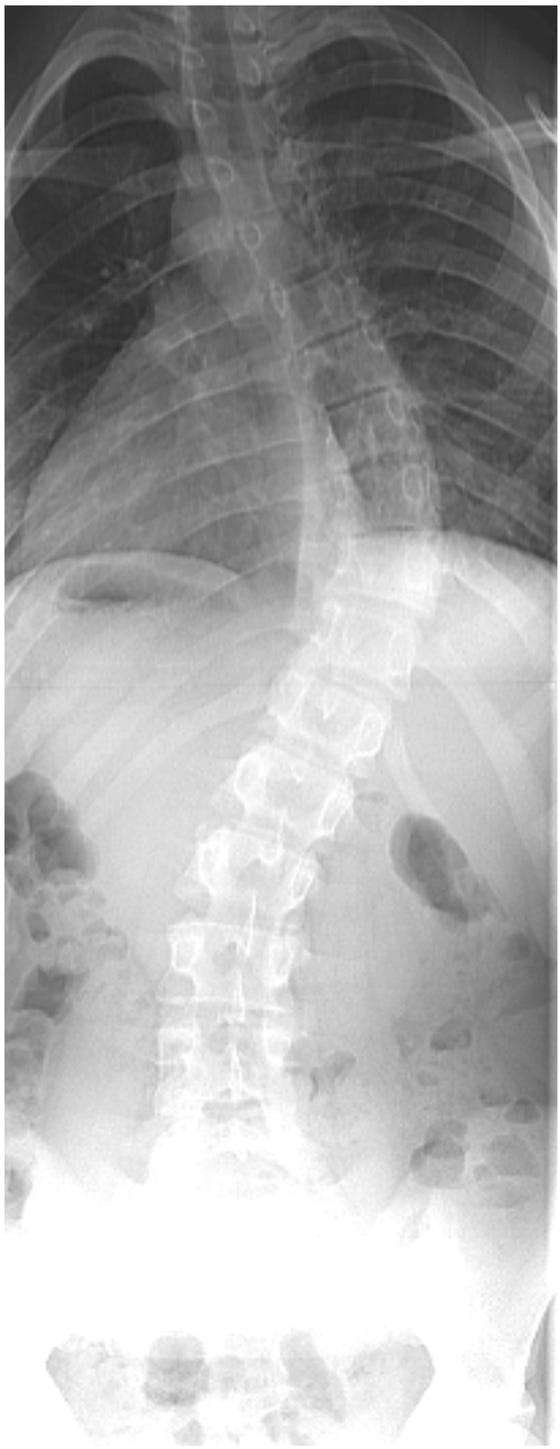

De wervelkolom wordt vastgezet met behulp van metalen staven en schroeven. Op sommige plaatsen maakt de chirurg de wervels beter passend door wat bot weg te halen. Dit zorgt ervoor dat alles stevig vast groeit.

Op de röntgenfoto’s kun je zien hoe de wervelkolom er voor en na de operatie uit ziet.

Figuur 1: scoliose voor de operatie

Figuur 2: scoliose na de operatie